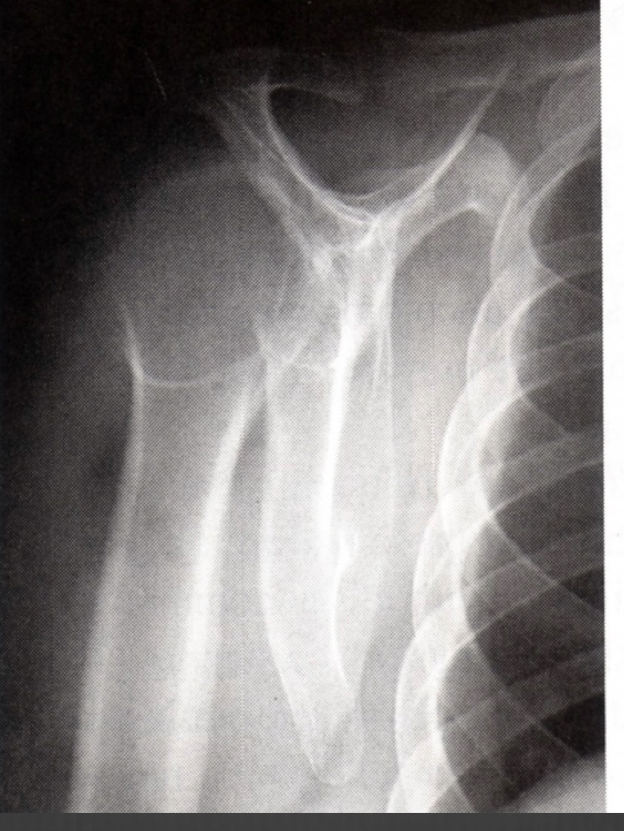

MC site for clavicle fx

what views do you need

Middle third is #1 MC Fx site

need to ask for AP and angeled view

common clavicle fx site in elderly

Distal third – common in elderly

because they fall on the shoulder straight down